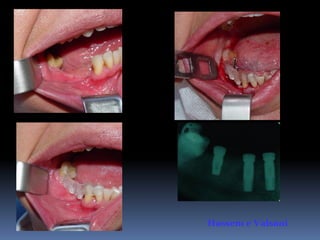

Guia cirúrgico

•Permite o posicionamento ideal da fresagem

através de orifício em guias transparentes

•Utilização de tubos, cones ou somente orifícios

realizados por fresas

•Liberdade controlada da fresa

Hassem e Valsani